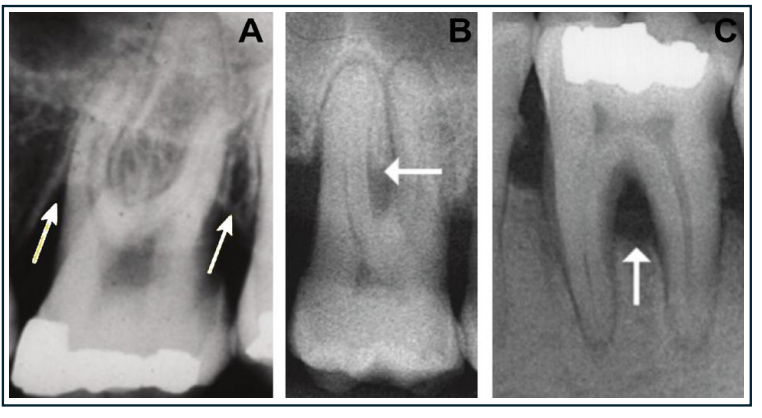

Facteurs Endodontiques

Une pathologie d’origine pulpaire peut générer une lésion radio-claire interradiculaire par élargissement du desmodonte ou via des canaux accessoires communiquant avec le plancher de la chambre pulpaire. Le diagnostic différentiel lésion parodontale / lésion endodontique / lésion endo-paro est fondamental.

L’examen radiographique est indispensable :

- Le cliché rétro-alvéolaire est préférable à l’OPG (orthopantomogramme), qui présente de nombreuses distorsions géométriques

- Le Cone Beam (CBCT) offre une supériorité diagnostique démontrée pour la détection des lésions interradiculaires, toutes configurations confondues. Son indication doit être réservée aux situations cliniques complexes ou lorsqu’un diagnostic différentiel s’impose.

2. Se contenter de l’OPG pour le diagnostic radiographique

Pourquoi c’est problématique : L’orthopantomogramme génère des distorsions géométriques significatives dans les zones molaires. Les lésions interradiculaires précoces ou modérées y sont souvent invisibles ou sous-estimées.

Bonne pratique : Privilégier le cliché rétro-alvéolaire pour l’évaluation de routine. Recourir au Cone Beam pour les cas complexes nécessitant un bilan tridimensionnel.

6. Méconnaître l’origine endodontique d’une lésion furcatoire

Pourquoi c’est problématique : Une lésion radio-claire en zone interradiculaire d’origine pulpaire (via canaux accessoires ou perforation) peut être diagnostiquée à tort comme une atteinte parodontale, avec des conséquences thérapeutiques radicalement différentes.

Bonne pratique : Réaliser systématiquement des tests de vitalité pulpaire face à toute lésion furcatoire d’apparition rapide ou asymétrique. En cas de doute, le traitement endodontique prime.

Problématique identifiée : La sonde de Nabers traverse la furcation mésiale de part en part (classe III de Hamp). La dent présente une vitalité pulpaire douteuse (test froid négatif). Le Cone Beam révèle une destruction osseuse tridimensionnelle sévère avec composante verticale de 8 mm (sous-classe C). Suspicion d’atteinte combinée endo-paro.

Point pédagogique : Face à une lésion interradiculaire sévère, le diagnostic différentiel endo-paro est incontournable. Le CBCT apporte ici une valeur diagnostique que le cliché 2D ne peut pas fournir. Le contrôle des facteurs de risque systémiques est aussi important que le traitement local.

Comment différencier une lésion interradiculaire d’origine parodontale d’une lésion d’origine endodontique lors de l’examen clinique ?

Le test de vitalité pulpaire est l’élément clé : une dent vitale avec atteinte de furcation évoque une lésion parodontale pure. Une dent nécrosée avec image furcatoire oriente vers une origine endodontique (via canaux accessoires ou perforation). Dans les formes combinées endo-paro, les deux étiologies coexistent et doivent être traitées séquentiellement, en commençant par le traitement canalaire.

Comment le Cone Beam améliore-t-il le diagnostic des lésions interradiculaires par rapport à la radiographie conventionnelle ?

Le Cone Beam (CBCT) offre une vision tridimensionnelle permettant de visualiser les défauts osseux dans les trois plans de l’espace. Il est supérieur aux radiographies conventionnelles pour détecter les lésions précoces, quantifier précisément la destruction verticale et apprécier la morphologie radiculaire. Son indication doit cependant rester ciblée : situations cliniques complexes, diagnostic différentiel difficile ou planification chirurgicale, en raison du surcoût et de l’irradiation plus importante.